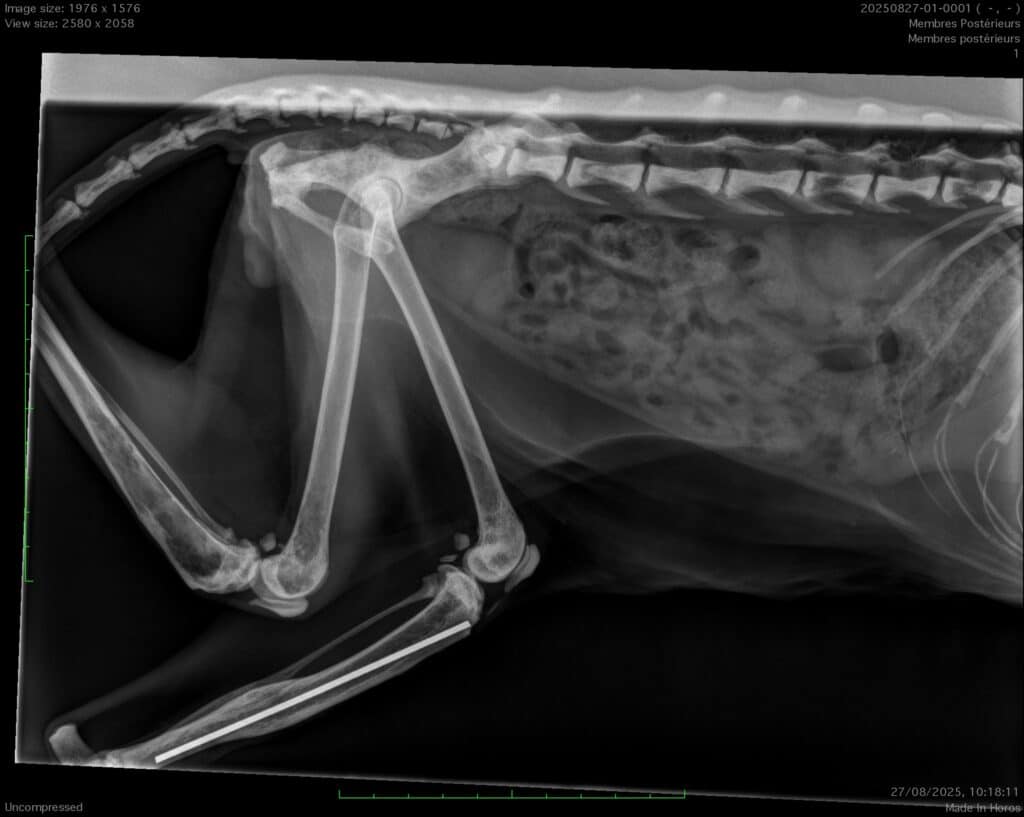

Chat de 17 ans présentant les mêmes symptômes que le précédent, difficultés locomotrices , ne sait plus sauter…

Sur la radio on peut voir une ancienne fracture traitée par enclouage centromédullaire mais aussi des taches noires sur certaines vertèbres, au niveau du bassin et du tibia non encloué. Il s’agit malheureusement d’un cancer.

La radio démontre toute son utilité, chat même âge, mêmes symptômes mais diagnostic , pronostic et traitement différents